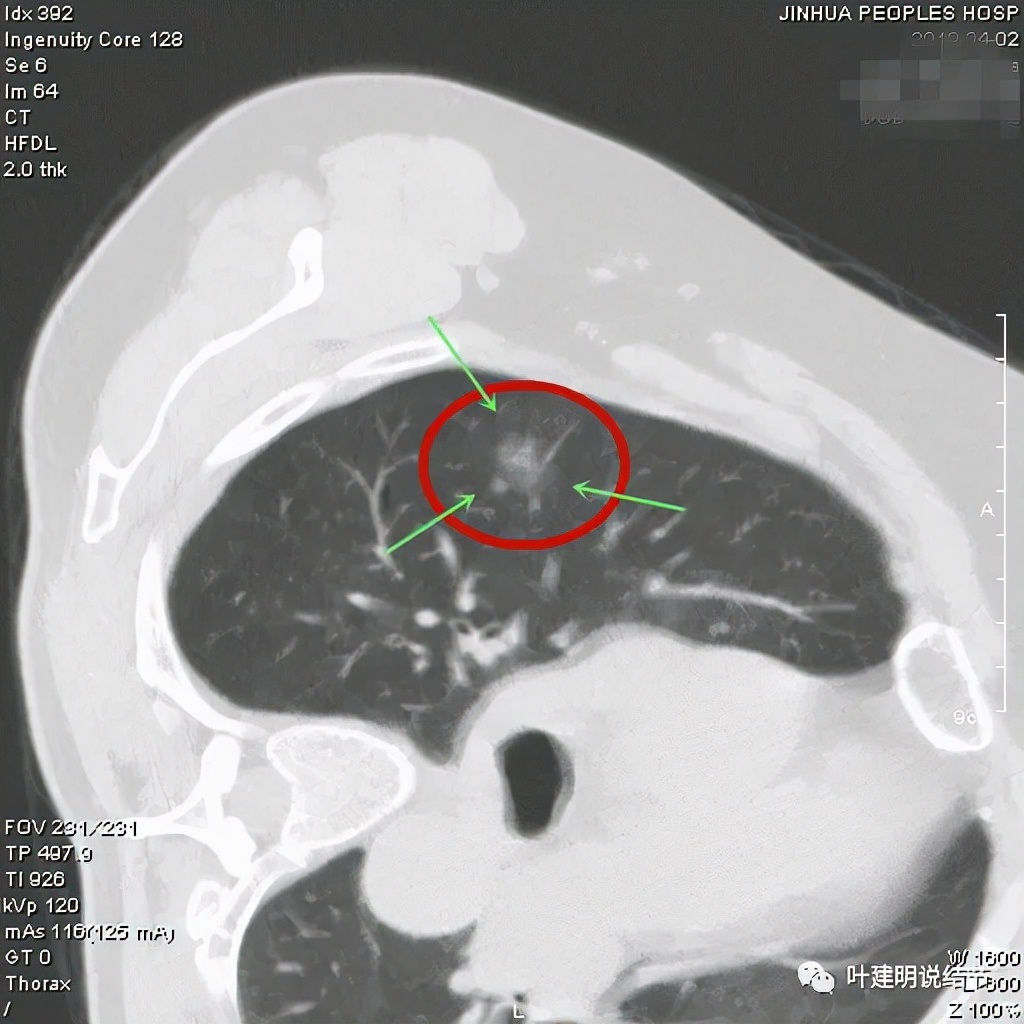

从以上靶扫描图像上看,给人的印象是肿瘤范畴的结节,是混合磨玻璃结节,但磨玻璃部分的密度偏低,有的边缘显模糊,中间有点状高密度,也有微小血管进入,应该至少微浸润性腺癌可能性大。持续存在已经2月余,位置又还靠边上的,可考虑手术切除。下面再来瞧瞧后处理重建的图像:

上图非常不舒服,病灶边缘有毛刺(蓝色箭头),中间有偏实性成分(粉色箭头所指),整体看密度不均杂乱

上图示明显的血管进入(桔色箭头),而且进入病灶后散大模糊,不是穿行;病灶内有高密度区域(粉色箭头)。但事后分析,绿色箭头所指的磨玻璃部分密度仍是过低,且边缘显模糊,与浸润性腺癌可能不是太符合。

以上三图均示典型的混合磨玻璃,实性成分杂乱,整体密度杂乱,并有血管征,是较为典型的浸润性腺癌影像表现。